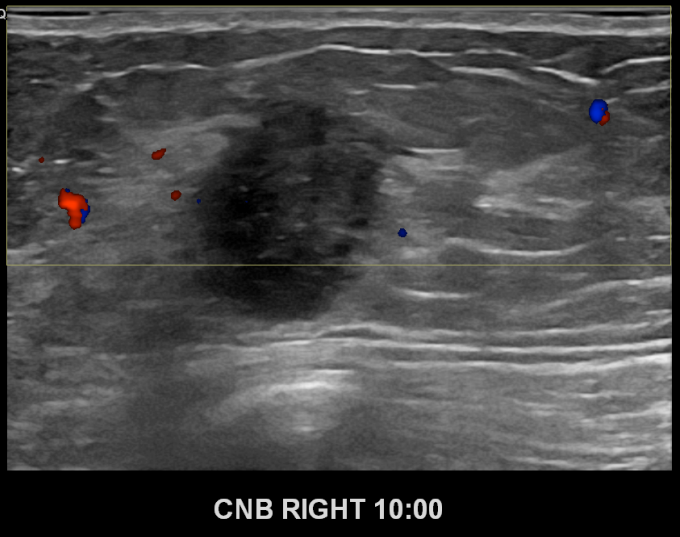

아산유외과개원후 695번째 유방암진단

상기환자 우측유방에 딱딱한 멍울이만져져 내원하신 50대여성분으로 좌측유방의 혹 조직검사시행후 유방암 진단되었습니다